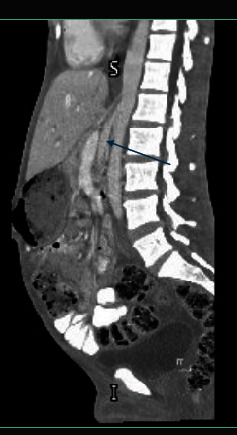

Nutcracker syndrome (NCS), a rare but impactful vascular condition, emerges from the compression of the left renal vein by adjacent major arteries, leading to a diverse array of symptoms such as hematuria, flank pain, and renal challenges. Highlighting the case of a 30-year-old male with an atypical presentation of NCS, this report explores the diagnostic complexities arising from its varied presentations and therapeutic options. It emphasizes the critical role of computed tomography (CT) in unveiling the underlying vascular constriction. Through this lens, the case underscores the necessity of considering NCS in the differential diagnosis of abdominal pain, advocating for a prompt and accurate diagnosis to guide effective management strategies, ranging from conservative approaches to surgical intervention. This stresses the importance of heightened awareness and ongoing research for optimizing patient outcomes in the face of this elusive condition.